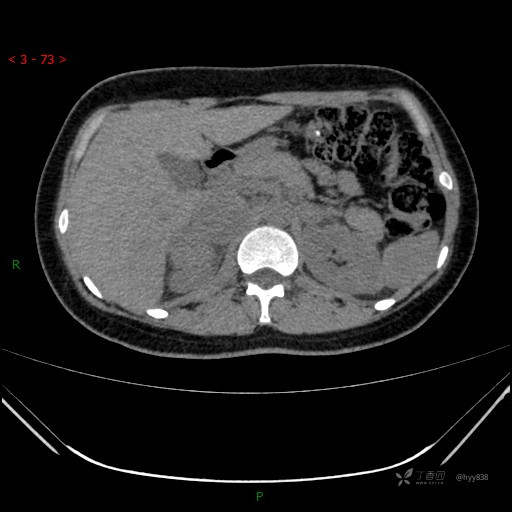

肾上腺CT平扫